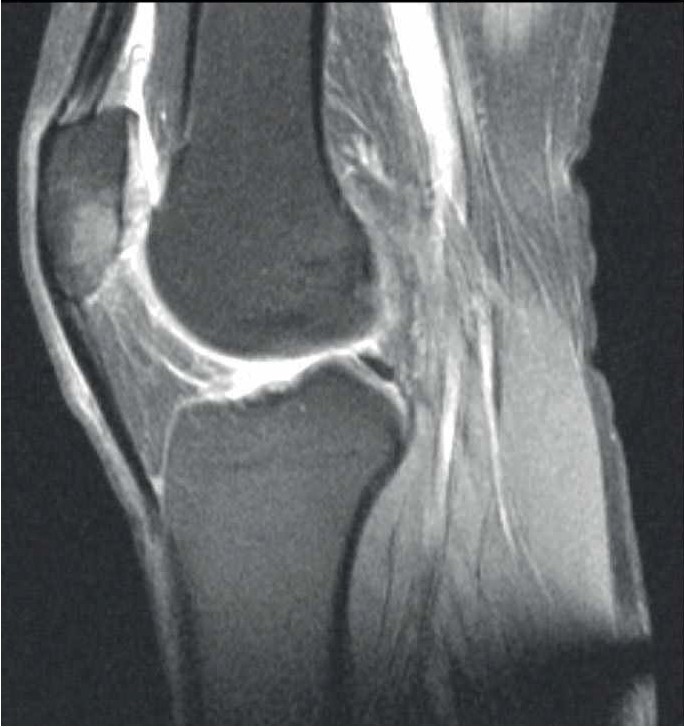

Спустя 6 мес стала отмечать боль (8 баллов по ВАШ) в области нижнего полюса надколенника в покое и при нагрузке, резкую боль – в нижнем полюсе надколенника при активном и пассивном сгибании в коленном суставе. Обратилась в травматолого-ортопедическое отделение. Семейный и соматический анамнез не отягощен. В феврале 2022 г. провели МРТ коленного сустава, обнаружен асептический некроз нижнего полюса надколенника (рис. 2). Выполнена артроскопия коленного сустава с декомпрессией очага некроза.

Рис. 2. МРТ коленного сустава у пациентки Б. Диагноз – асептический некроз нижнего полюса надколенника.

В раннем послеоперационном периоде пациентка отмечала снижение боли (интенсивность – 3 балла по ВАШ). Назначены терипаратид подкожно 20 мкг 1 раз в сутки в течение 2 мес и ношение ортеза на коленный сустав. На контрольный осмотр не явилась.